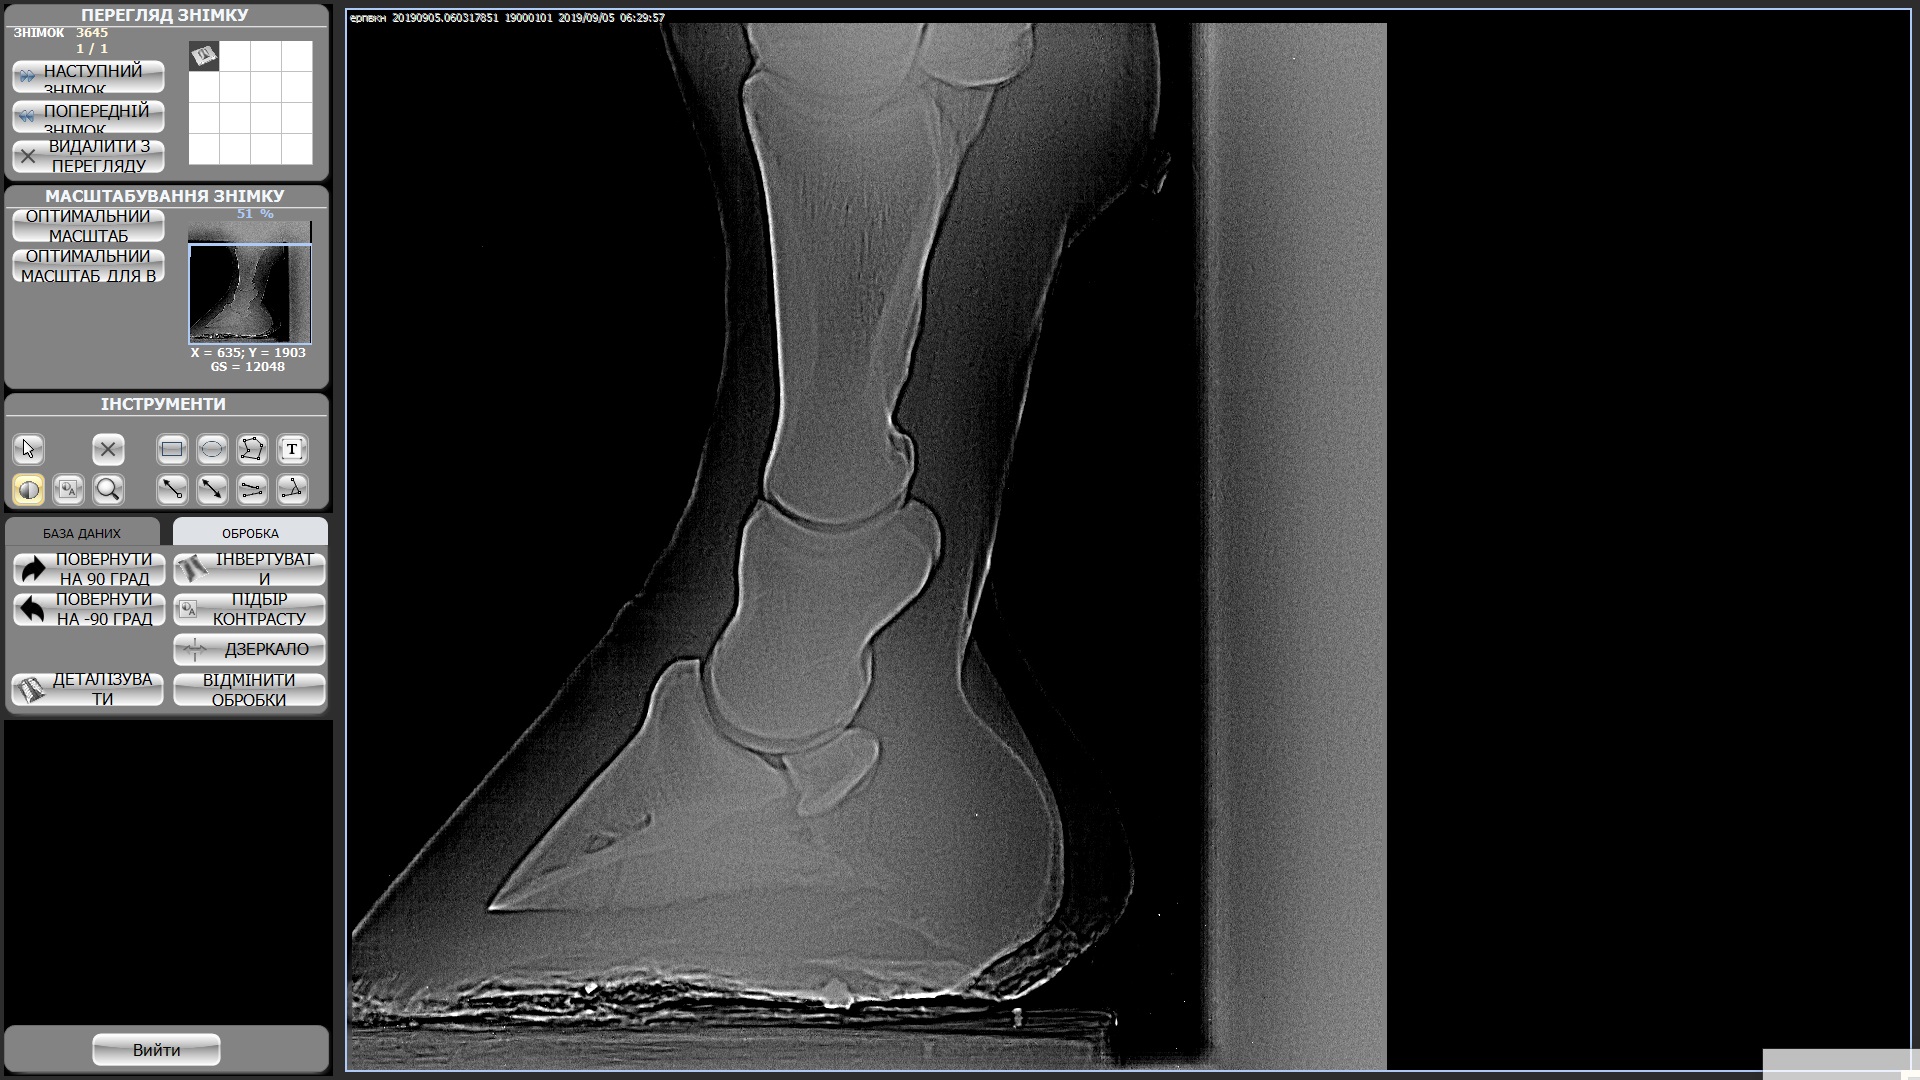

Мерин 7 лет, купили в этом году, смотрели с ветом и делали рентгены ног, прикрепила к теме. Были микротравмы суставов из за чего появляются наливы (мягкие шишки) на суставах всех 4х ног. Приглашала другого вета сказал менять постав подковами ортопедическими, так и сделали после чего конь захромал на правый перед и оба зада, проходили так неделю и сняли подковы - хромота ушла, но копытные остались налитыми, как и шишки не сошли. Вроде бы все было хорошо на протяжении 2х недель, наливы не сошли, но конь на них не жалуется. И вот на днях ходили в поля (только шагом), пару раз нас напугала то машина, то веточка и он подрывался немного. На следующее утро хромает на все 4, щупали мышцы и смотрели наливы изменений нет но конь хромает на все 4 и немного теплые копытные((((

Студдебекер 3 ЗЛ.jpg494 KB · Просмотры: 366 -

студебеккер 2 ЗП.jpg404.4 KB · Просмотры: 370 -

СтудебеккерПЛ.jpg489.8 KB · Просмотры: 327 -

Студебеккер ПП.jpg528.2 KB · Просмотры: 411 -